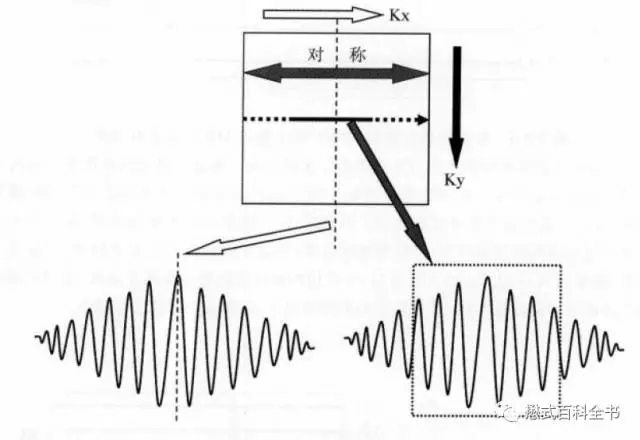

K空间的对称性,其实理解起来也不难。在频率编码方向(Kx)方向,我们采集的是很多信号采样点,模拟成连续信号后,是一个对称的信号变化曲线。

图9:K空间频率编码方向的对称性

图9:K空间频率编码方向的对称性